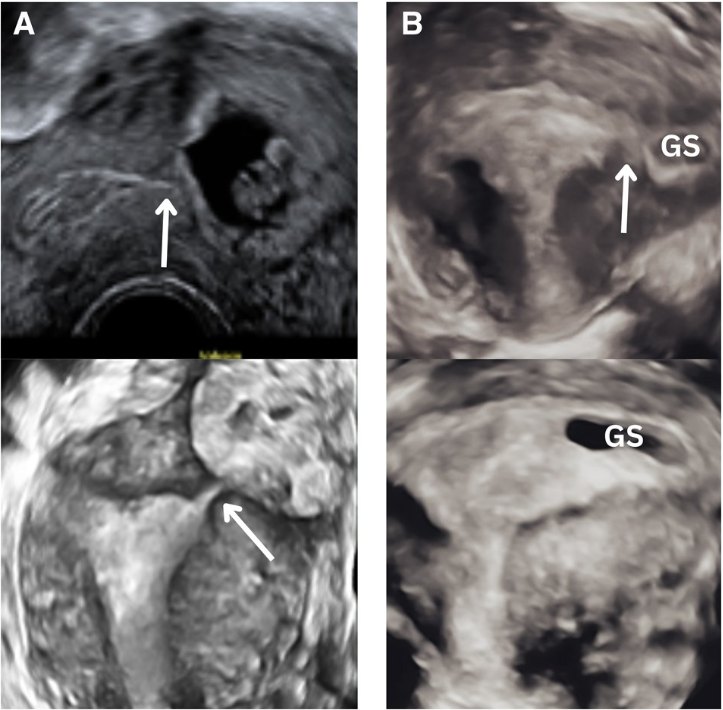

Ektopična trudnoća nastaje kada se gestacija razvija potpuno ili delimično izvan endometrijalne šupljine. Iako su tubarne implantacije najčešći i klinički dobro poznat oblik bolesti, atipične lokalizacije i parcijalne ektopične trudnoće predstavljaju značajan dijagnostički izazov. Kod pacijentkinja sa progresivnom trudnoćom posebno je važno postaviti sigurnu dijagnozu, jer najteža dijagnostička greška može biti nenamerni prekid normalne eutopične trudnoće.

Izbor između ekspektativnog pristupa, koji je kod hemodinamski stabilnih pacijentkinja često adekvatan, i aktivne intervencije zavisi od precizne procene veličine, lokalizacije i vaskularizacije mesta implantacije. Pored neposrednog kliničkog zbrinjavanja, važno je i individualno savetovanje o riziku ponovne ektopične trudnoće, kao i prepoznavanje mogućih psiholoških posledica koje ovaj događaj može imati za pacijentkinju.